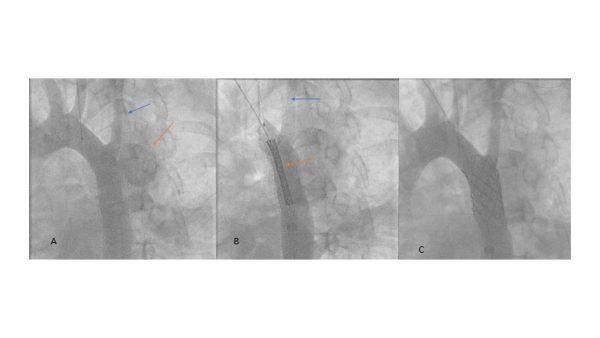

- Initial aortic angiogram shows the pseudoaneurysm (orange arrow), and its relationship to the left subclavian artery (blue arrow) (Video 8)

- Szabo technique: anchoring wire in the left subclavian artery (blue arrow), and covered stent (orange arrow) (Video 9)

- Post stent placement angiogram shows the complete covering of the pseudoaneurysm and patency of the left subclavian artery (Video 10).

Case presentation 2: Another example using the Szabo technique to protect the left subclavian artery while treating an aortic arch pseudoaneurysm.

Figure 2

Figure 2: